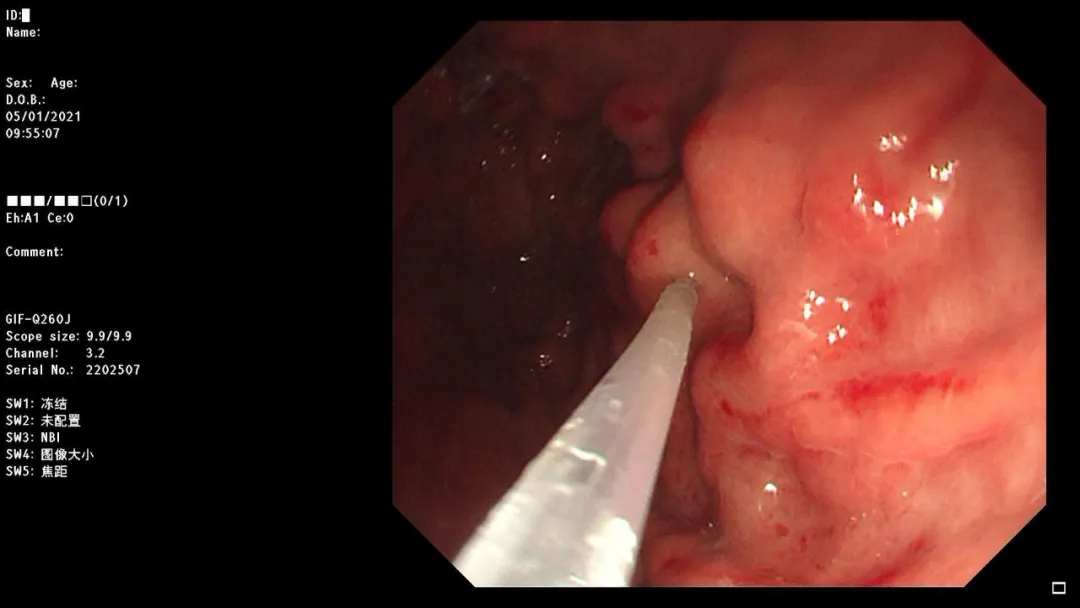

急诊胃镜示:十二指肠球部可见异物,予异物钳取出,检查诊断:急诊异物取出术。